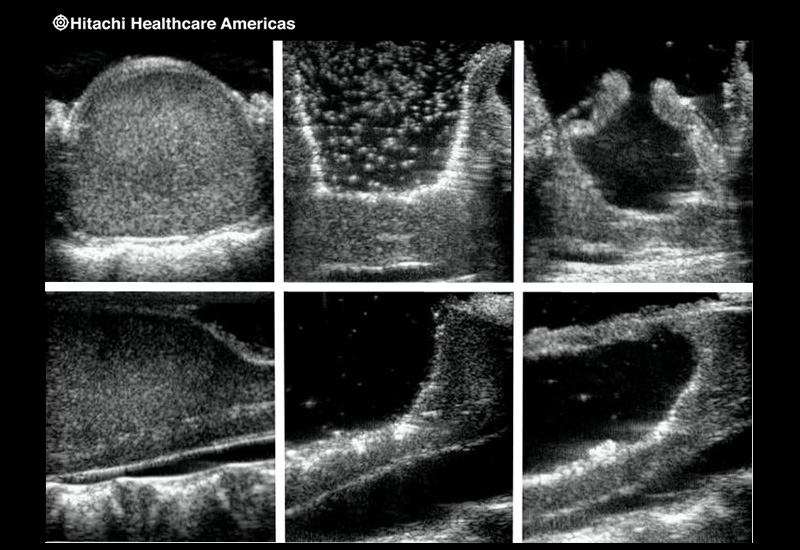

Superior guidance for all applications

Fujifilm Healthcare Americas is committed to designing tools that help surgeons navigate inside the human body and provide the necessary information to immediately make critical surgical decisions.

Fujifilm Healthcare's dedication to Surgeons provides outstanding ultrasound technology, professional support and the specialized tools necessary to best perform comprehensive real-time ultrasound imaging in Breast Surgery, General Surgery, Laparoscopic Surgery, Neurosurgery, Robotic Surgery and Surgical Oncology.